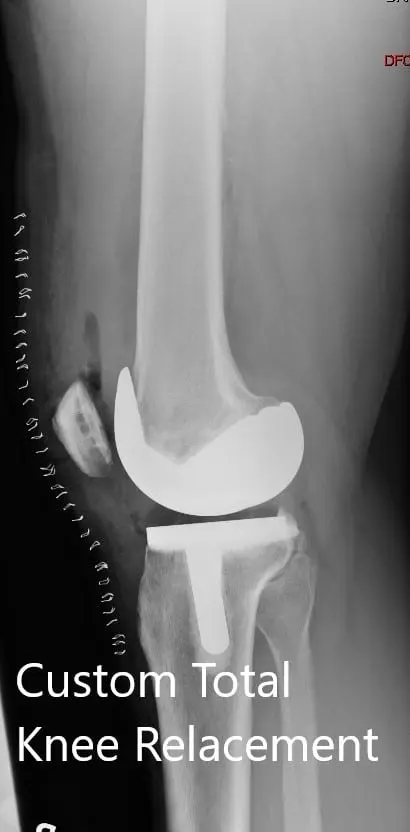

Postoperative X-ray showing the AP view of both knees

Postoperative X-ray showing the AP view of both knees.